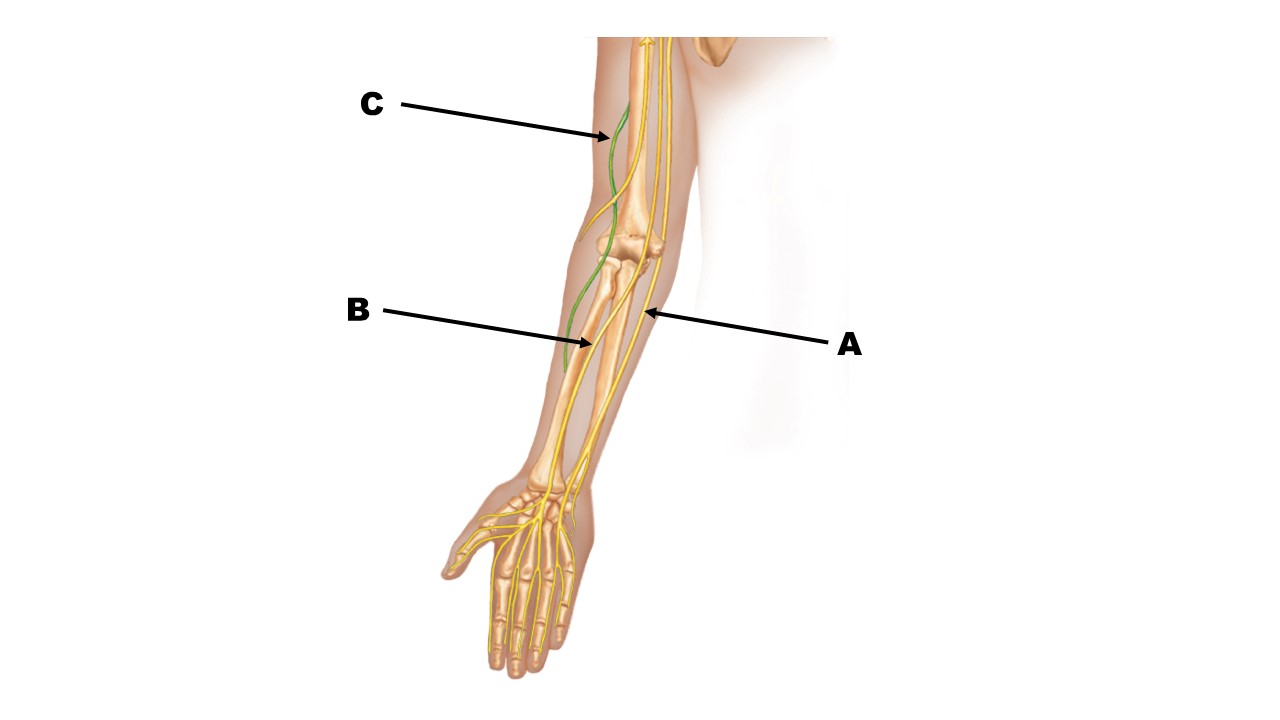

The nerve at the tip of arrow B is the _______ nerve.

median

The nerve at the tip of arrow A is the _______ nerve.

ulnar